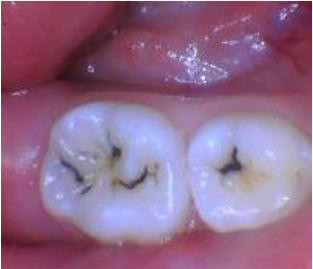

SDF is a clear liquid that is applied to cavities. It contains silver, which is antimicrobial, and fluoride, which helps decrease the solubility of tooth structure and prevent further demineralizing. Together, SDF helps strengthen areas of dental decay and decreases the quantity of harmful bacteria, ultimately preventing existing cavities from growing larger and new cavities from forming. The silver portion of SDF stains tooth decay permanently black.

- Primary molars treated with SDF